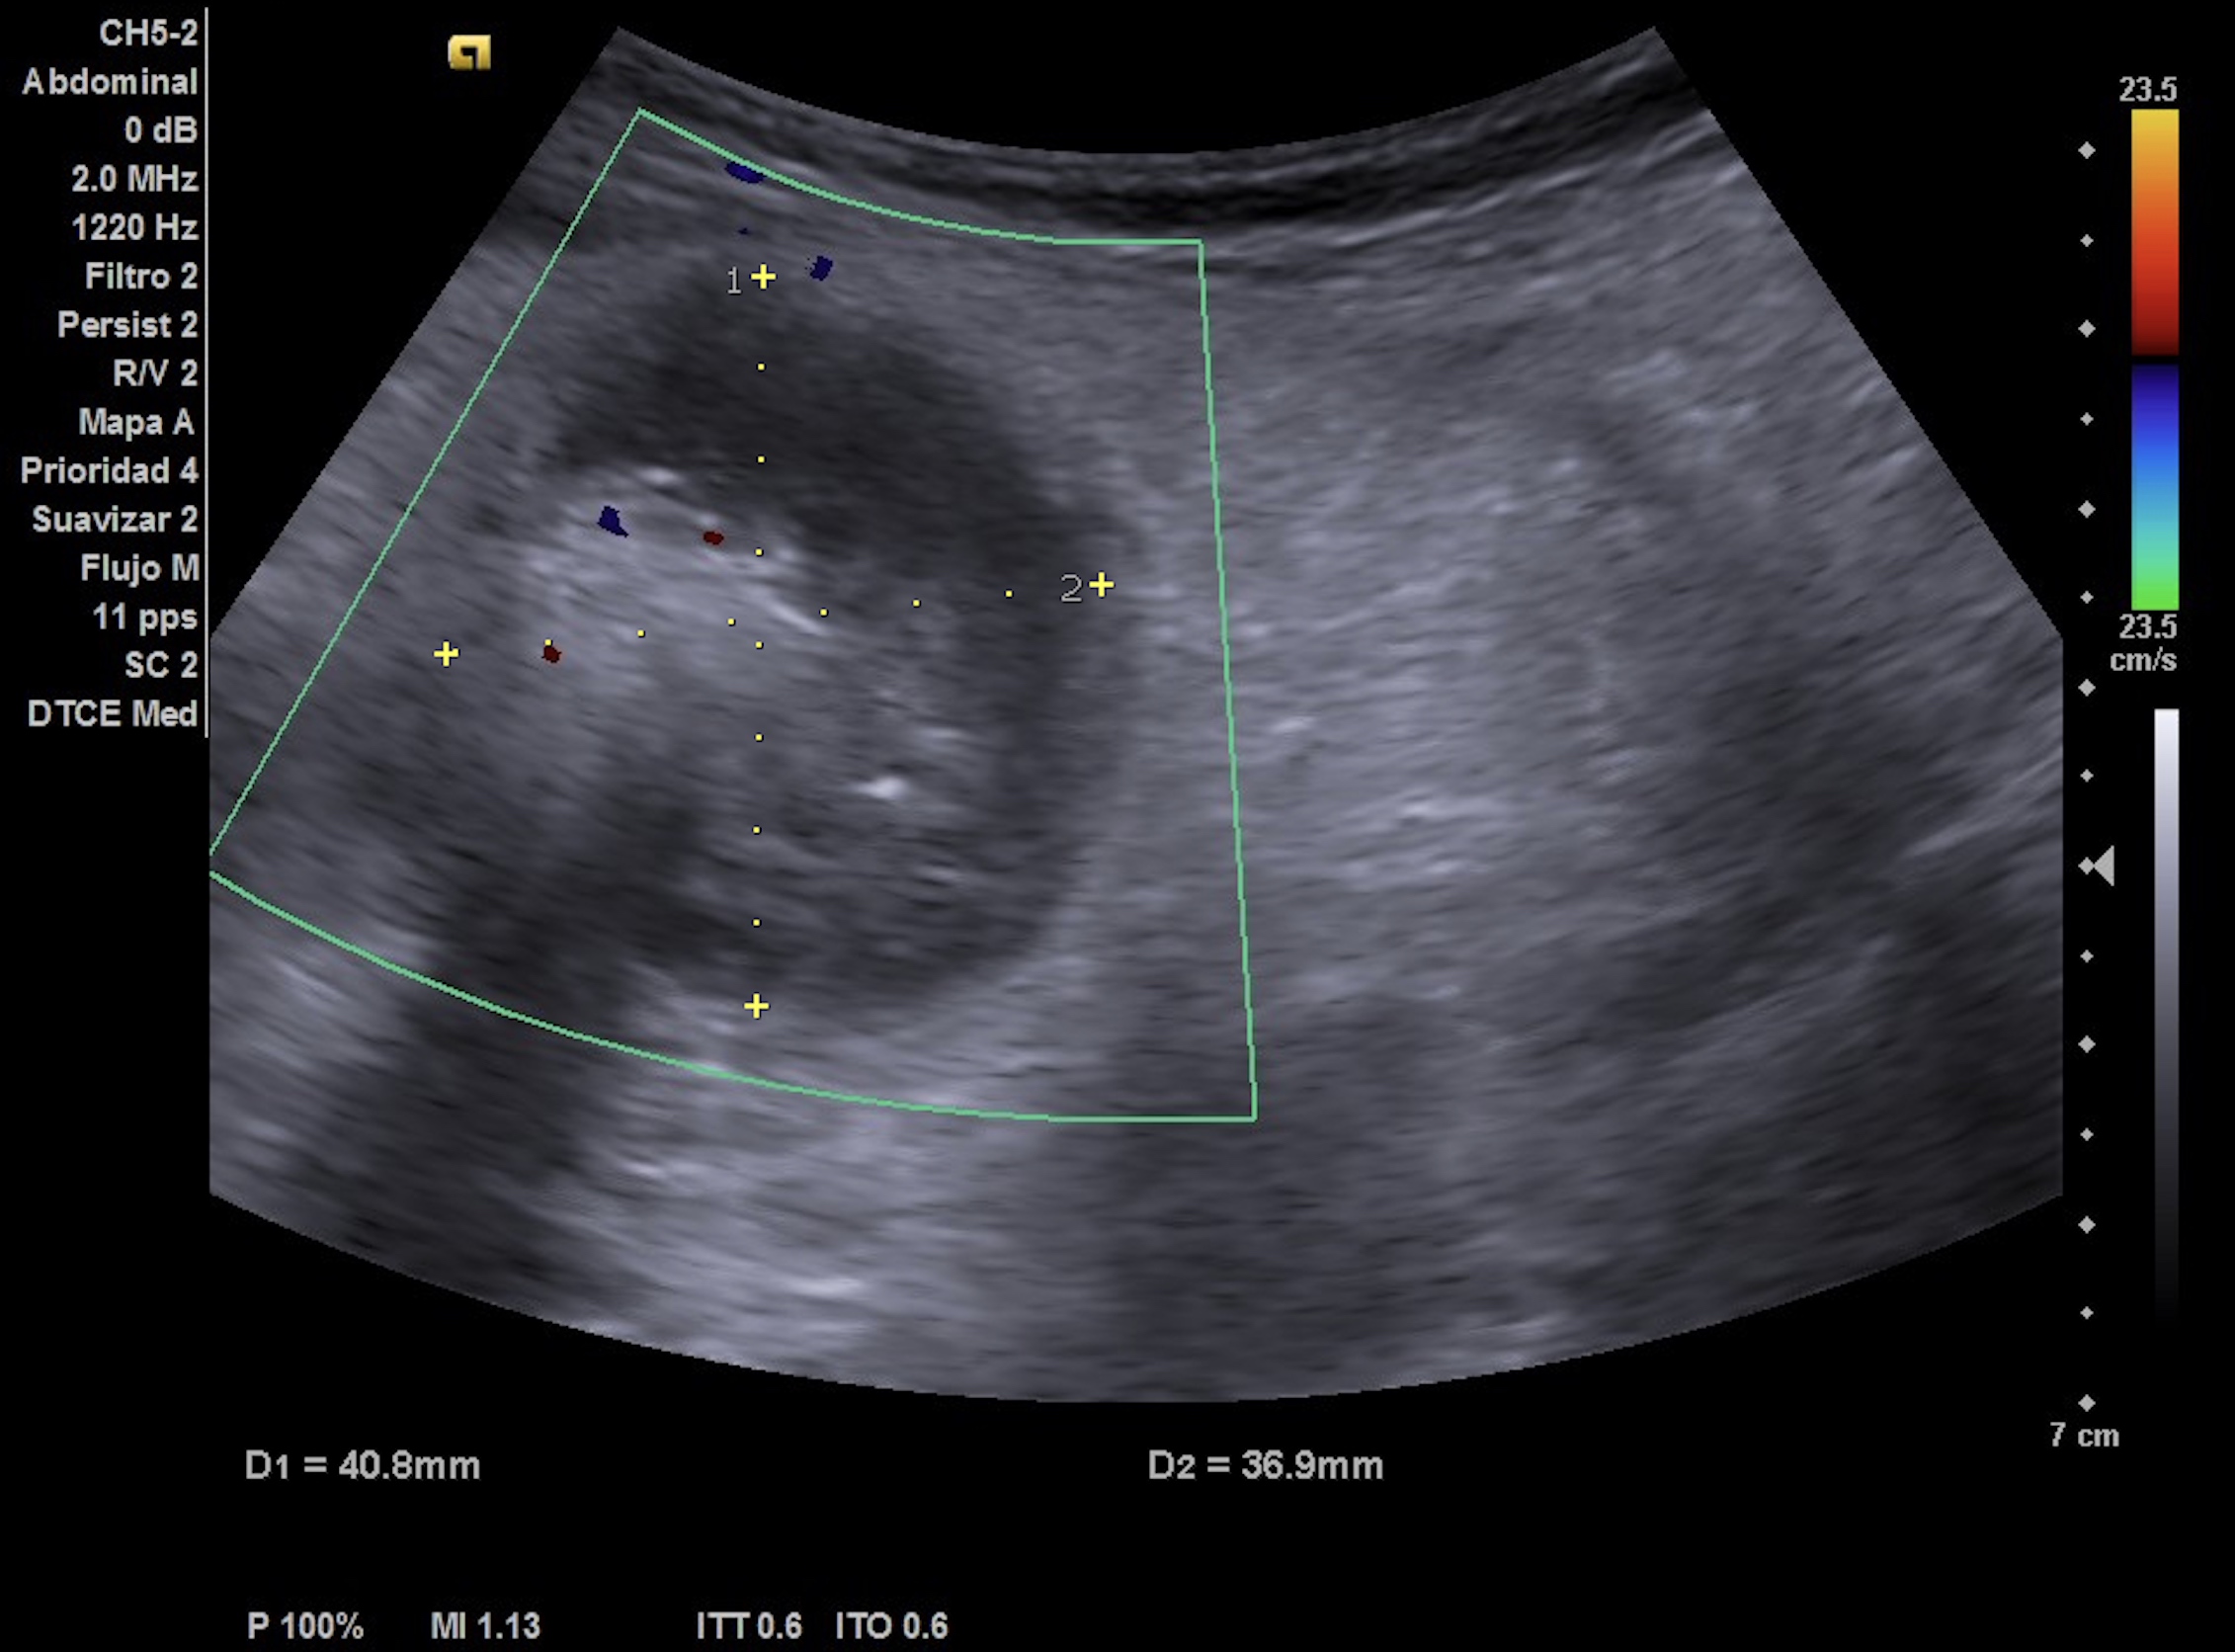

- Hígado de tamaño y eco-estructura normal. Riñón derecho normal. Imagen localizada anterior a riñón derecho, redondeada-ovalada, hipoecoica con zonas hiperecoicas en su interior, vascularizada probablemente compatible con signo de pseudo-riñón con sospecha de neoplasia de colon.